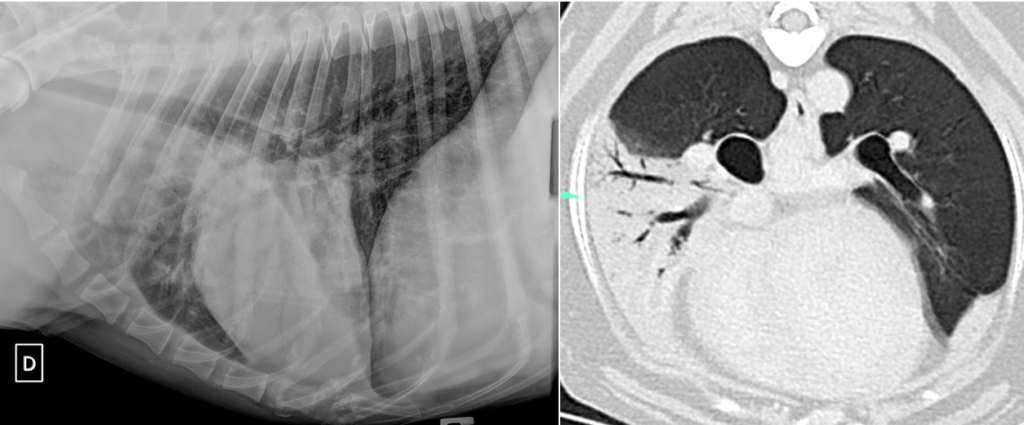

Figure 1 et 2 : opacification alvéolaire du lobe crânial gauche en radiographie à gauche (opacification alvéolaire lobaire avec bronchogramme et signe lobaire caudalement) et en tomodensitométrie à droite (consolidation alvéolaire lobaire du lobe moyen droit).